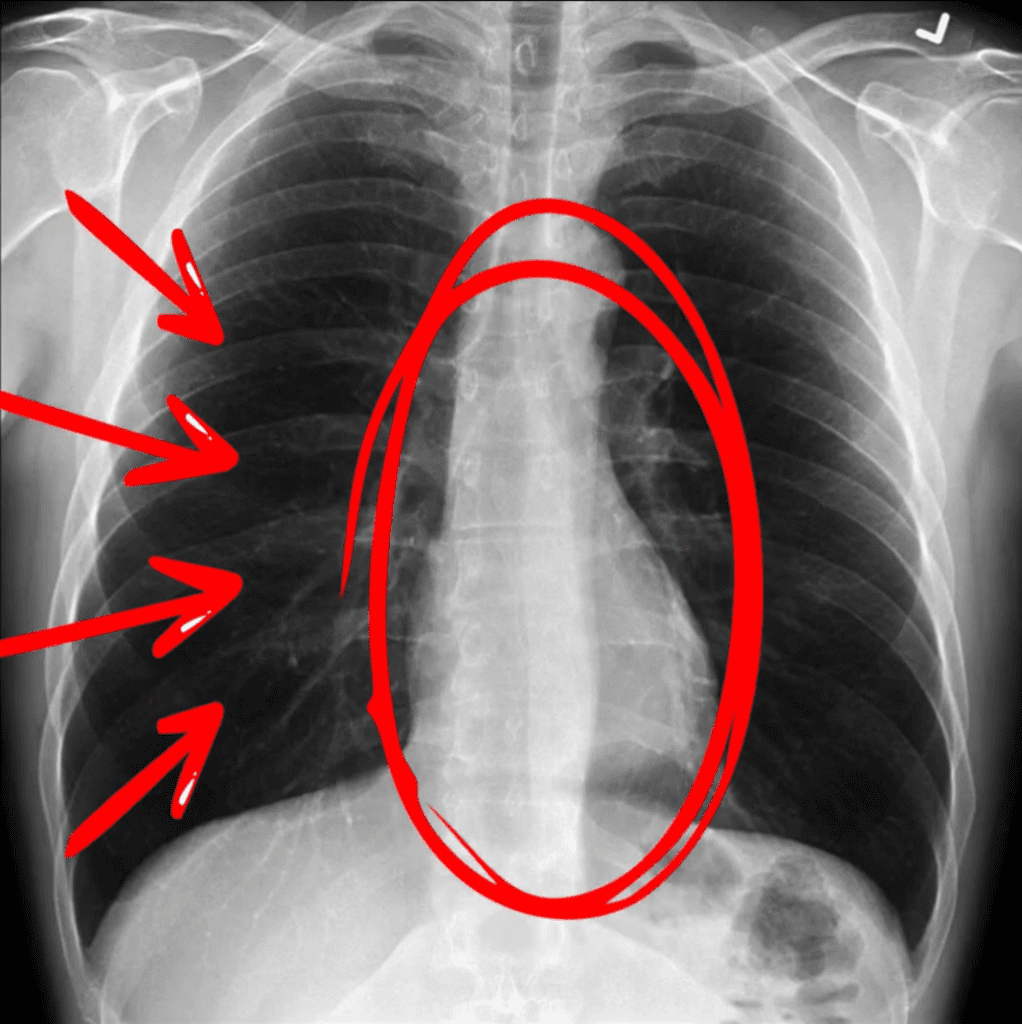

Radiografia toracică

Radiografia pulmonară este considerată standardul de aur pentru confirmarea pneumoniei, în special în cazurile complicate sau când diagnosticul clinic este incert. Aceasta ajută nu doar la confirmarea infecției, ci și la diferențierea tipurilor de pneumonie, ceea ce poate orienta tratamentul.

Cum interpretăm o radiografie toracică?

Radiografia pulmonară normală:

- În imagine, inima este vizibilă în partea centrală (cercul roșu din imagine)

- Zonele negre reprezintă aerul din plămâni, ceea ce indică o funcționare normală a acestora ( săgețile roșii din imagine)

- Oasele (coastele, claviculele și coloana vertebrală) apar mai albe, datorită densității osoase.